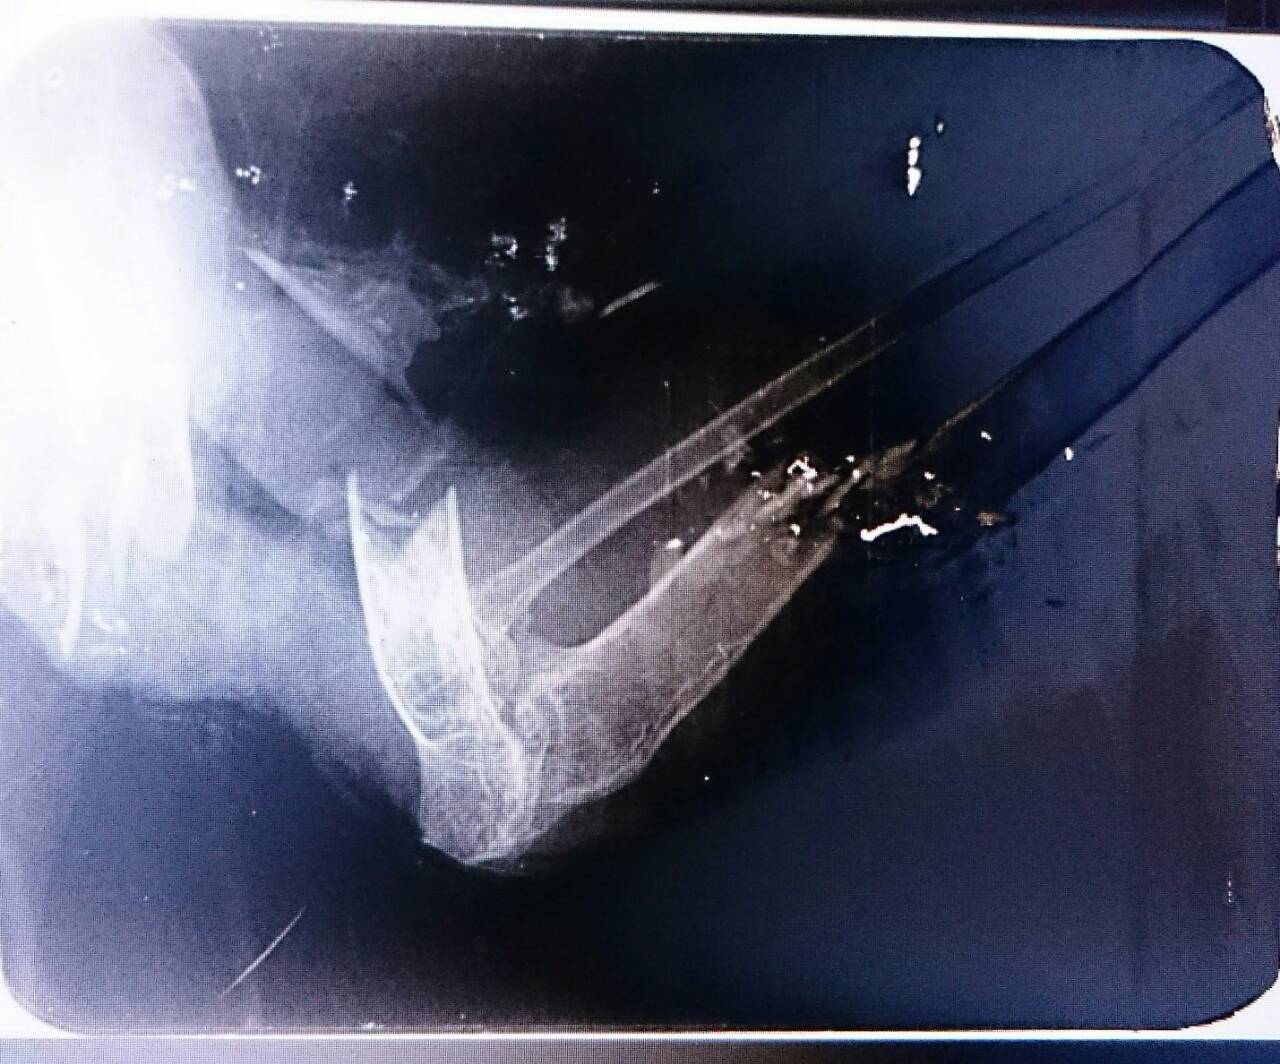

Привезли ворону 2девушки из Санкт-Петербурга, почему именно к нам, мы не знаем, но воронка переехала жить к нам, в естественной среде обитания жить не смогла бы, ведь она по ряду причин потеряла крыло.